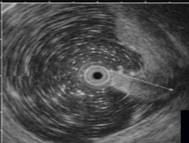

Распространенный рак желудка. Во II группе при визуальном осмотре 282 пациентов диагностирован распространенный рак желудка и согласно классификации указана его макроскопическая форма. У всех больных рак был подтвержден морфологически, причем дифференцированные аденокарциномы были у ,9%) пациентов, низкодифференцированные – у ,1%).Общий эндосонографический критерий всех форм распространенного РЖ – это наличие неоднородного гипоэхогенного образования, которое исходит из слизистой оболочки, с глубиной инвазии в мышечный или серозный слой, или выходит за пределы стенки желудка, с нарушением дифференцировки между слоями (рис.2).

Рис.2. 71 год. Блюдцеобразный рак нижней трети тела желудка.

Гистология – умереннодифференцированная аденокарцинома:

а - визуальная картина блюдцеобразного рака; б - эндосонограмма блюдцеобразного рака, гипоэхогенное образование с инвазией в серозную оболочку.